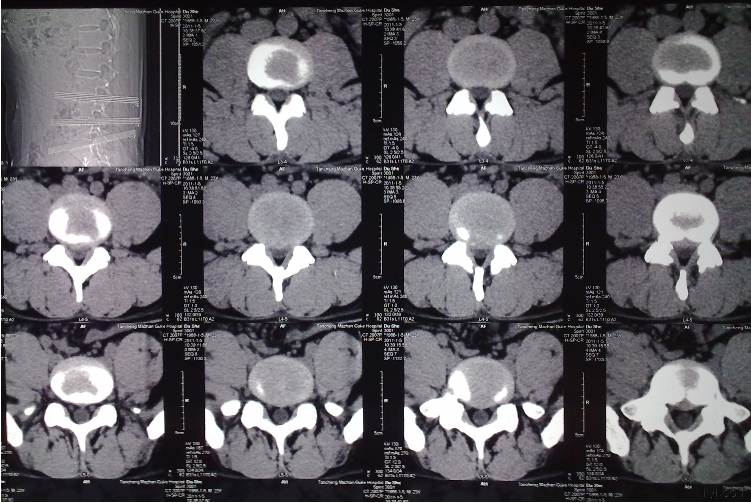

②腰椎CT(腰椎椎体CT或腰椎间盘CT)

图片 14336